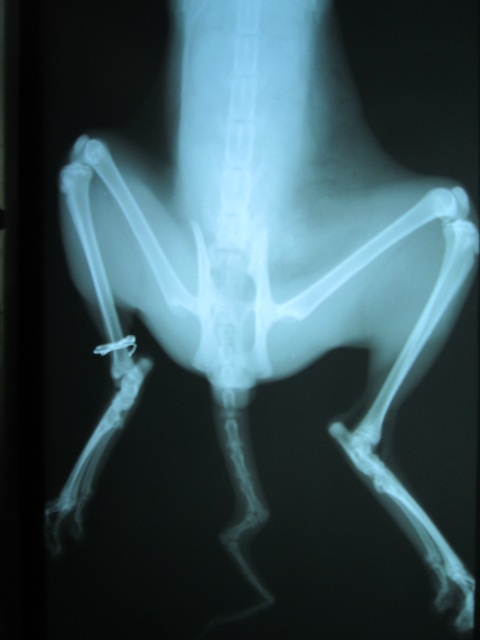

主題: 被車撞的可憐小黃貓 申請者姓名: 趙慧曄 花色: 申請日期: 2013-04-23 22:11:32 申請者部落格: 申請者臉書網址: http://www.facebook.com/profile.php?id=100000504239033 所在縣市/合作醫院: 屏東縣/愛生動物醫院 治療費用: 3500元 需求人數: 8人 已結案 (2013-06-27 14:33:08) 報名人員: Nata Chen(已付款)、Rachel Huang x2(已付款)、Ping Meng(已付款)、Vivienne Peng(已付款)、Winnie Chou(已付款)、Liyun Chang(已付款)、邱惠卿(已付款)、 候補人員: 動物病情說明: 在龍泉村崇文國中旁遭車子撞擊的小黃貓當晚救援先安置一晚一早送愛生醫院檢查治療麻醉照X光無骨折但腹部尾部大片瘀青~經醫師打針住院治療已無大礙結紮!!選離救援他的地方離200公尺TNR友善的住戶區野放放回!!謝謝大家的愛心!! 動物近況說明: 今天早上選在崇文國中200公尺旁友善的TNR住戶區野放嚕!!動作非常迅速表示復原得非常好喔!!